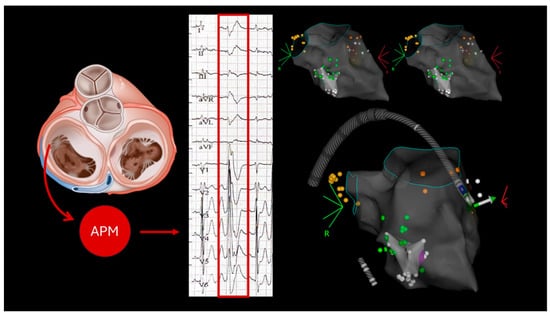

2.1. Case 1

2.2. Case 2

2.3. Case 3

2.4. Case 4

2.5. Case 5